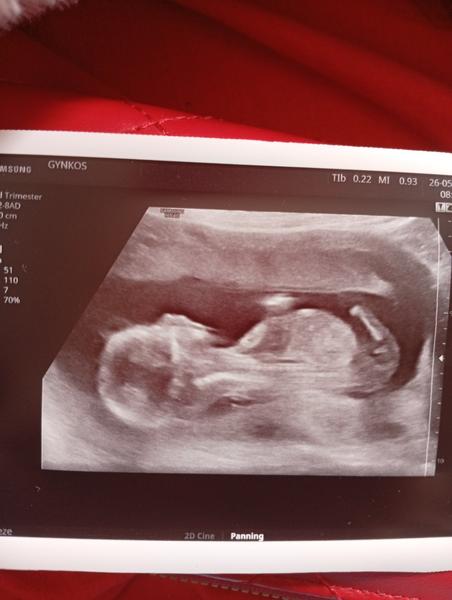

Dobrý den. Na ultrazvuku byl vidět ,, pindík, vrchem a stal🙈 Doktor řekl že tipuje kluka a za 3 tydny to pry bude vidět líp. Mam doma 4 holky🙈🤣 nepoznáte to Podle hrbolku nějakého? 🙈

@verusak2025 tak jak to dopadlo? 🙂